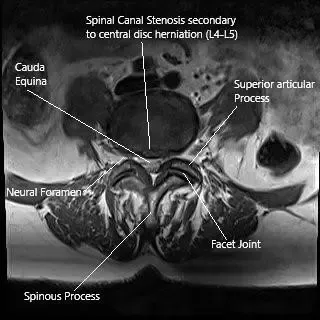

Resonancia magnética de la columna lumbar en una hernia discal central en la sección axial.

- Resonancia magnética: El estándar de oro para diagnosticar hernia de disco, compresión nerviosa o anomalías de tejidos blandos.